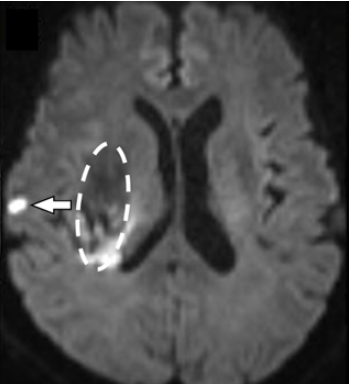

(図1)脳出血(破線囲み部分)を発症した時の“隠れた小さな脳梗塞”(矢印)

急性脳内出血におけるDWI陽性病変と小血管疾患との相関:コホート研究 DWI-Positive Lesions in Acute Intracerebral Hemorrhage and Their Correlation With Small Vessel Disease A Cohort Study

Diffusion-weighted imaging (DWI)–positive lesions are identified in 11%–45% of patients with acute intracerebral hemorrhage (ICH); however, their underlying mechanisms and clinical implications remain unclear. Moreover, the prevalence of these lesions before blood pressure lowering remains elusive. The aim of this study was to evaluate the prevalence, time-dependent changes, and associations of DWI-positive lesions with small vessel disease (SVD) markers and clinical outcomes in patients with acute ICH.

Among 872 patients, 114 patients (13.1%) exhibited DWI-positive lesions (mean age: 71.5 ± 12.9 years; female, 36.0%). The number of patients with DWI-positive lesions was lower among those who underwent MRI before acute-phase blood pressure lowering (45/444 patients [10.1%]) than among those who underwent MRI after blood pressure lowering (69/428 patients [16.1%]). Multivariable analysis revealed that DWI-positive lesions were significantly associated with time from ICH onset to imaging (adjusted odds ratio [aOR], 1.41; 95% CI 1.08–1.84), but not with blood pressure lowering (aOR, 0.92; 95% CI 0.51–1.65). DWI-positive lesions were also strongly associated with SVD markers and higher SVD severity scores. Furthermore, DWI-positive lesions were linked to unfavorable outcomes at 90 days (aOR, 1.70; 95% CI 1.04–2.80).

DWI-positive lesions are observed before blood pressure lowering, and their frequency increases over time. Their association with SVD markers highlights the role of advanced SVD in lesion formation. These lesions may worsen clinical outcomes, can potentially be helpful as prognostic imaging biomarkers, and may help guide optimal acute ICH management.